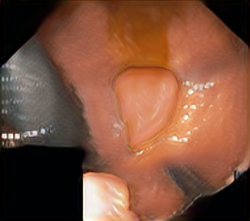

A few sample images and the corresponding masks of the polyp dataset in HyperKvasir are shown in Fig 2. The polyp images are RGB images. The masks of the polyp images are single-channel images with white () for true pixels, which represent polyp regions, and black () for false pixels, which represent clean colon or background regions. In this dataset, there are different sizes of polyps. The distribution of polyp sizes as a percentage of the full image size is presented in the histogram plot in Fig 3, and we can observe that there are more relatively small polyps compared to larger polyps. Additionally, a subset of this dataset was used to prove that the performance of segmentation models trained with small datasets can be improved using our SinGAN-Seg pipeline, and the whole dataset was used to show the effect of using SinGAN-Seg generated synthetic images instead of a large dataset which has enough data to train segmentation models. In this regard, this dataset was used for two purposes: